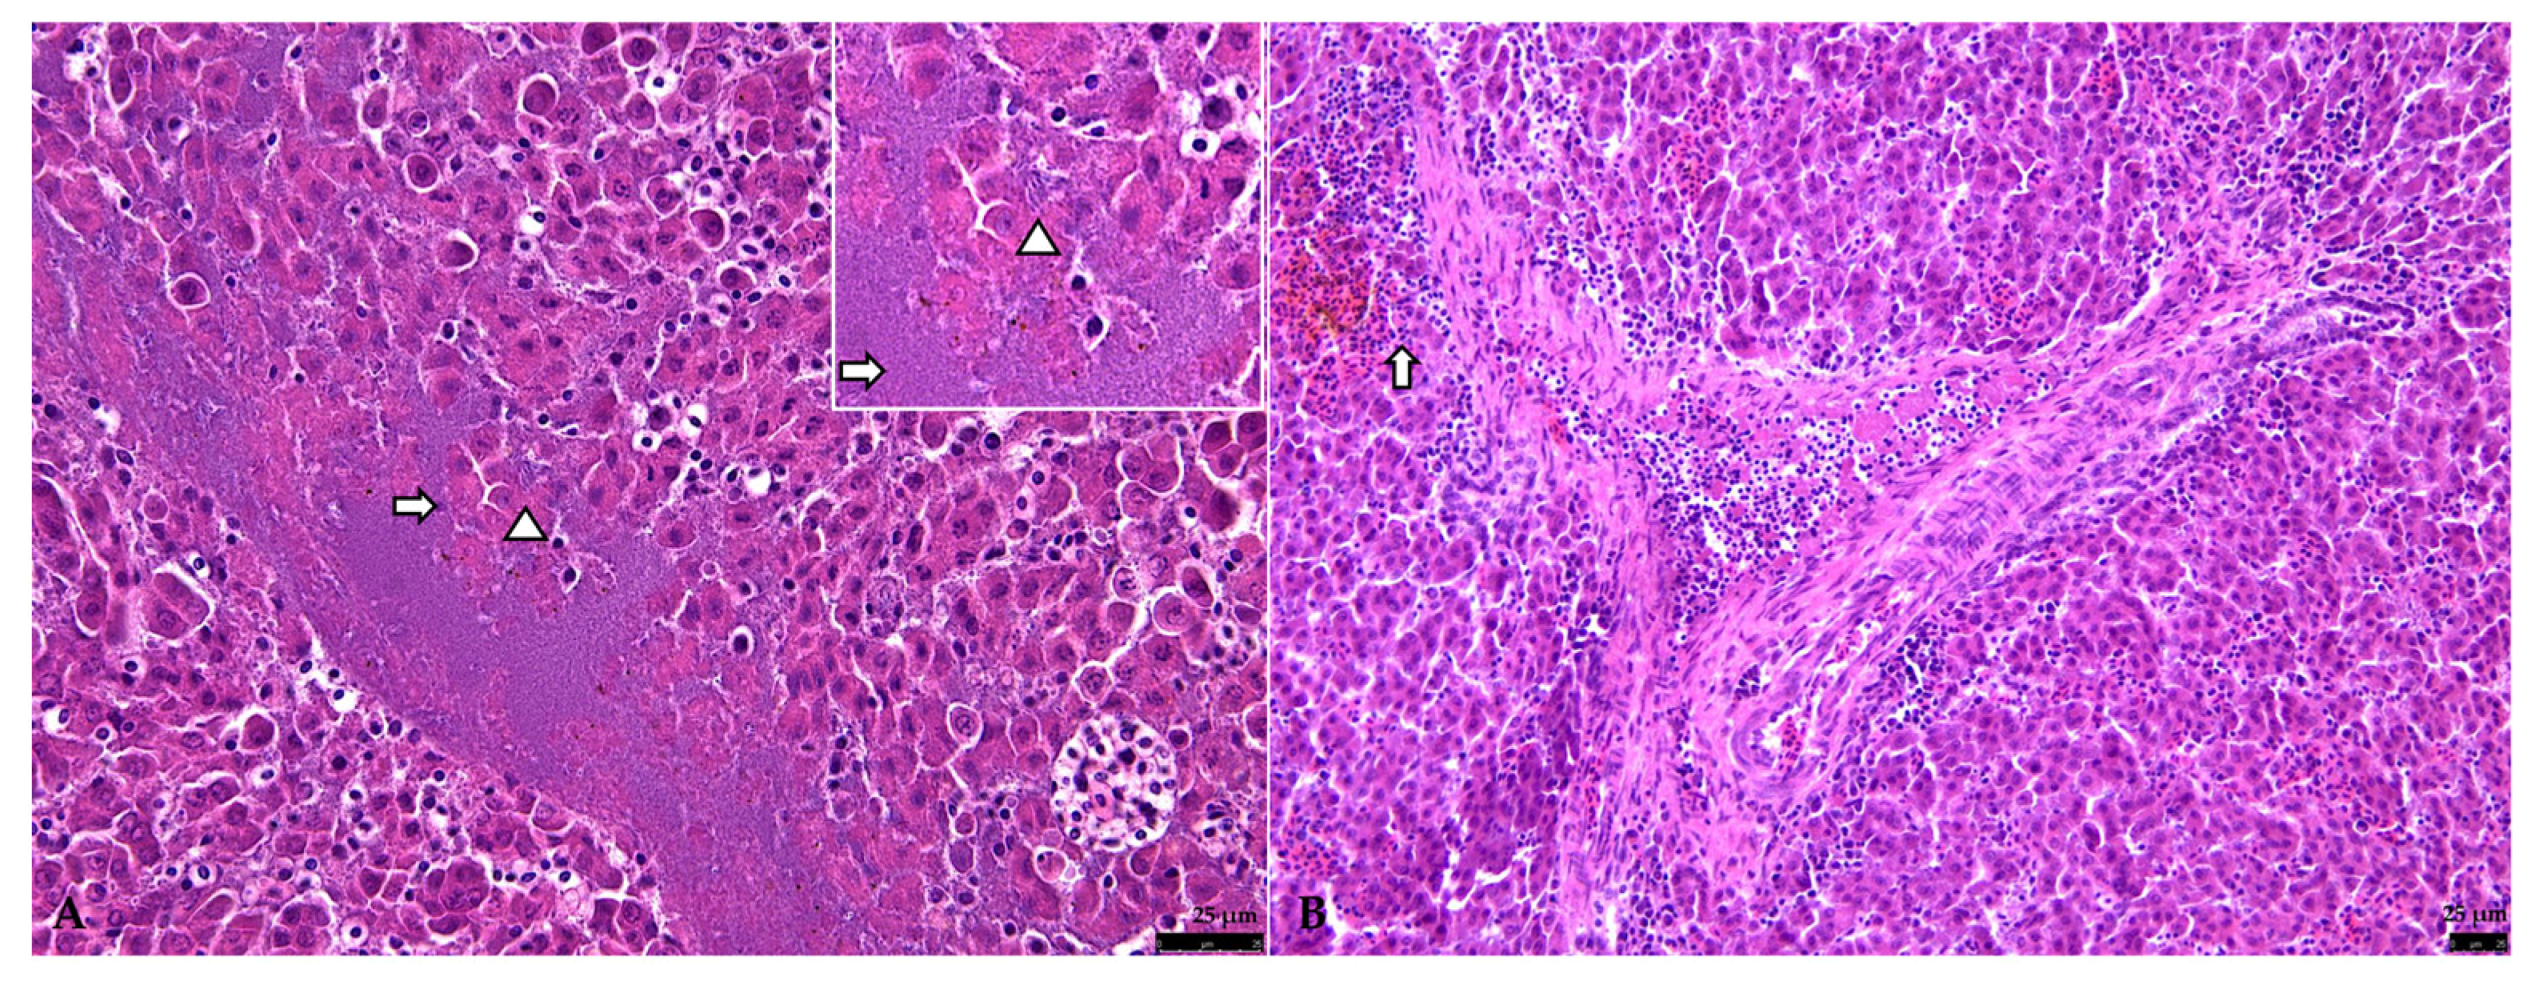

3.2.2. Liver